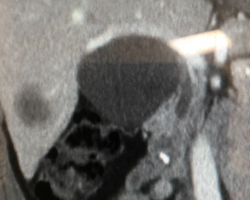

Resection of large retroperitoneal sarcoma including right and transverse colectomy and right hepatectomy